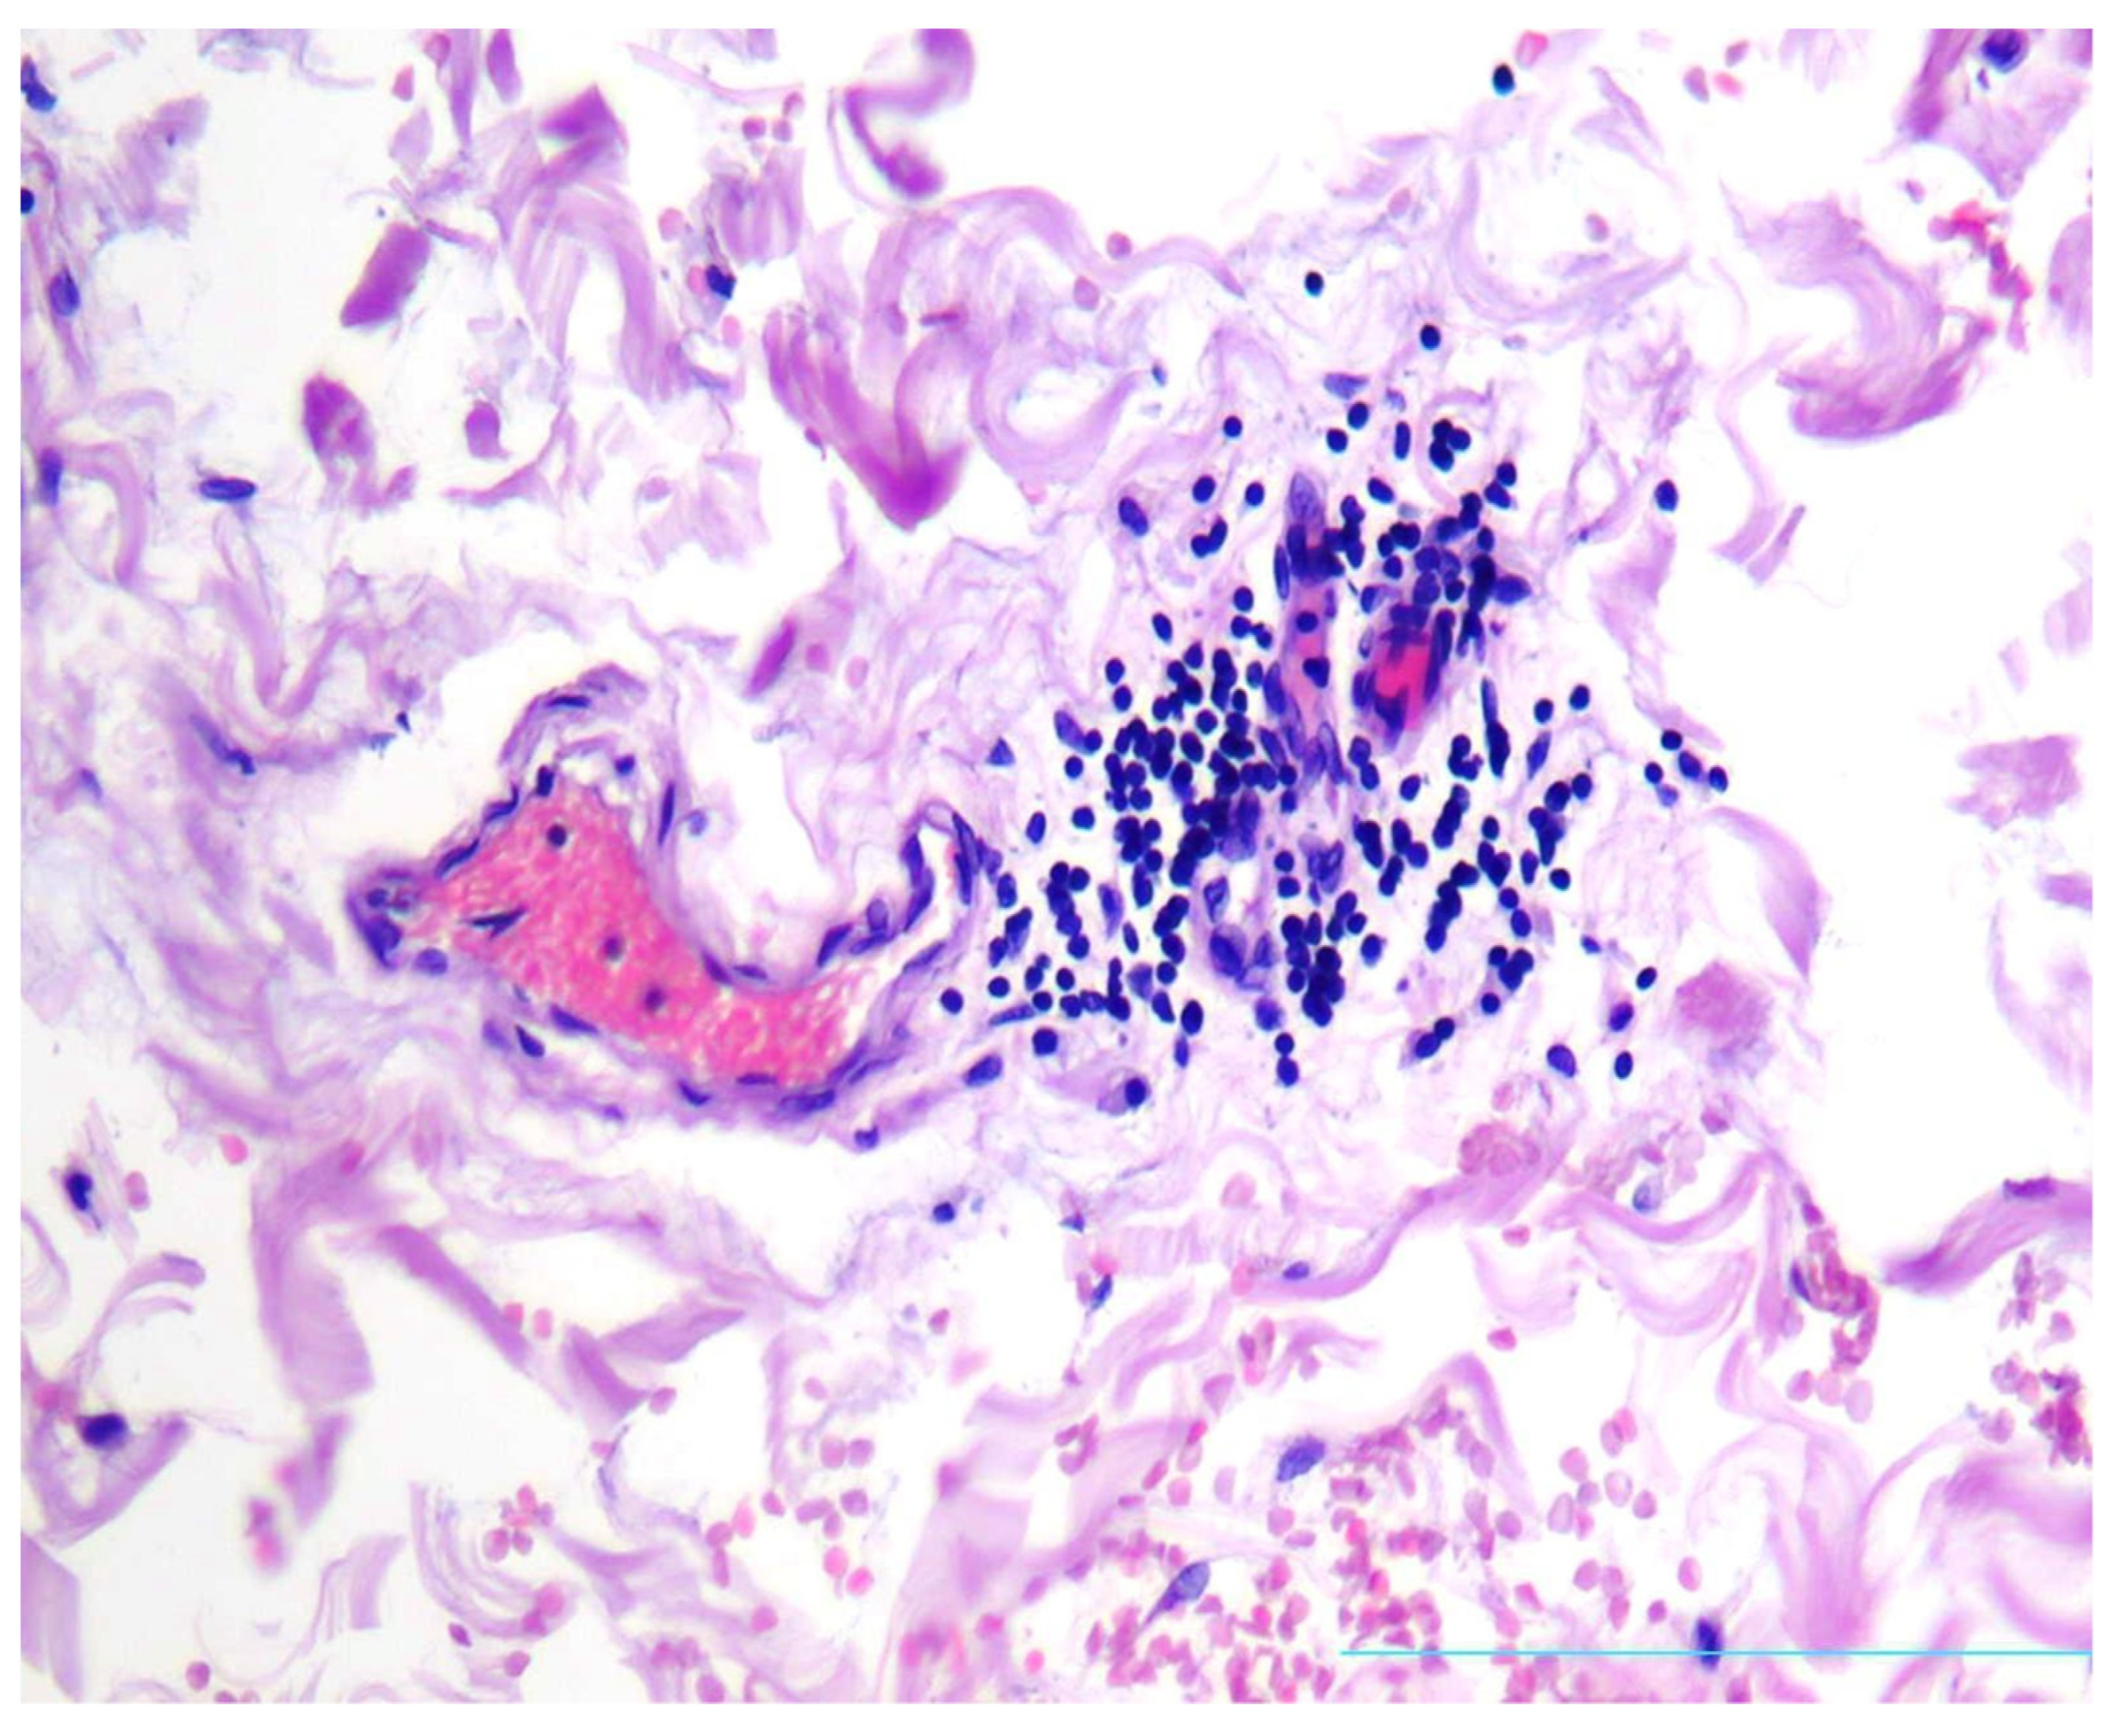

2. Case Presentation